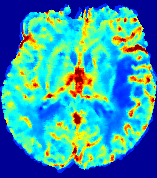

LesionRefer to captionRefer to captionRefer to captionRefer to captionRefer to captionRefer to caption𝐕rgbsubscript𝐕𝑟𝑔𝑏{\bf{V}}_{rgb}Refer to captionRefer to captionRefer to captionRefer to captionRefer to captionRefer to caption𝐕2subscriptnorm𝐕2{\|\bf{V}}\|_{2}Refer to captionRefer to captionRefer to captionRefer to captionRefer to captionRefer to captionRefer to caption3.53.53.52.82.82.82.12.12.11.41.41.40.70.70.70.00.00.0(mm/s)𝑚𝑚𝑠(mm/s)D𝐷DRefer to captionRefer to captionRefer to captionRefer to captionRefer to captionRefer to captionRefer to caption0.0200.0200.0200.0160.0160.0160.0120.0120.0120.0080.0080.0080.0040.0040.0040.0000.0000.000(mm2/s)𝑚superscript𝑚2𝑠(mm^{2}/s)Slice #1Slice #2Slice #3Slice #4Slice #5Slice #6

Figure 3: PIANO feature maps for one stroke patient, where the lesion is located in the left hemisphere. Top row: segmented stroke lesion region (white) on different slices, obtained from ISLES 2017. The corresponding slices for the PIANO feature maps are shown in the following rows.

For a better insight into an estimated velocity field 𝐕𝐕{\bf{V}} and diffusion field 𝐃𝐃{\bf{D}}, we compute the following maps: (1) 𝐕rgbsubscript𝐕𝑟𝑔𝑏{\bf{V}}_{rgb}: Color-coded orientation map of 𝐕=(Vx,Vy,Vz)T𝐕superscriptsuperscript𝑉𝑥superscript𝑉𝑦superscript𝑉𝑧𝑇{\bf{V}}=(V^{x},V^{y},V^{z})^{T}, obtained by normalizing 𝐕𝐕{\bf{V}} to unit length and mapping its 3 components to red, green, blue respectively; (2) 𝐕2subscriptnorm𝐕2\|{\bf{V}}\|_{2}: 222 norm of 𝐕𝐕{\bf{V}}; (3) D𝐷D: scalar field in Eq. 5.

Fig. 3 and Fig. 4 show the PIANO feature maps estimated from two ISLES 2017 patients: all are highly consistent with the lesion in both cases. Details of the blood flow trajectories are revealed in 𝐕rgbsubscript𝐕𝑟𝑔𝑏{\bf{V}}_{rgb} by the ridged patterns and the sharp changes of colors in the unaffected (right) hemisphere, while the flat patterns appearing within the lesion provide little directional information about the velocity and indicate low velocity magnitudes. Velocity magnitudes are more directly visualized via 𝐕2subscriptnorm𝐕2\|{\bf{V}}\|_{2}, from which one can easily locate the lesion where 𝐕2subscriptnorm𝐕2\|{\bf{V}}\|_{2} is low. D𝐷D also indicates lower diffusion values in the lesion, though with less contrast potentially due to the fact that it captures the accumulated effect of CA diffusion at the voxel-level.

3.2 Predicted CA Concentration

To better illustrate the prediction accuracy, and therefore the estimation accuracy of 𝐕𝐕{\bf V} and D𝐷{D}, of PIANO, we provide the corresponding predicted time-series of CA concentration images in Fig. 5 and Fig. 6 for the same patients in Fig. 3 and Fig. 4, respectively. We see that PIANO is capable of predicting the CA concentration given their initial state, indicating its ability to successfully capture 𝐕𝐕{\bf V} and D𝐷{D}. Note that although the concentration values for these two patients differ considerably, caused by the different total volume of injected CA, PIANO is still able to provide plausible estimates.